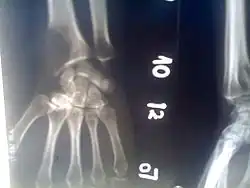

An osteolytic lesion (from the Greek words for "bone" (ὀστέον), and "to unbind" (λύειν)) is a softened section of a patient's bone formed as a symptom of specific diseases, including breast cancer and multiple myeloma. This softened area appears as a hole on X-ray scans due to decreased bone density, although many other diseases are associated with this symptom.[1] Osteolytic lesions can cause pain, increased risk of bone fracture, and spinal cord compression.[2] These lesions can be treated using bisphosphonates or radiation, though new solutions are being tested in clinical trials.